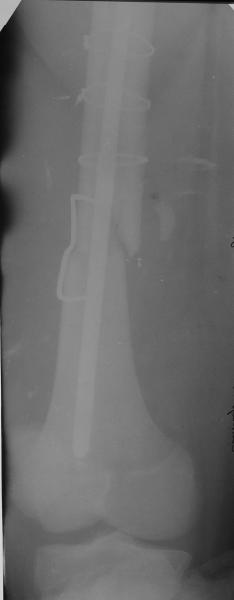

Уважаемые коллеги,пожалуйста, подумайте над следующим ребусом. В нашу клинику поступилпациент из области, 17лет, получивший травму в ДТП 25.08.04, открытый перелом бедра, при поступлении наложено скелетное вытяжение.

30.09.04 на операции выявлен вывих бедра и перелом голени на этой же стороне. Остесинтез бедра все же выполнен, и по заживлении раны пациент переведен к нам. Кроме того у пациента нейропатия седалищного нерва на этой же стороне. В нашей клинике планируется наложение аппарата таз-бедро, для постепенного низведения бедра с последующим открытым вправлением, замена фиксатора на запираемый гвоздь и блокируемый остесинтез голени. Вариант с первичным эндопротезированием мы не рассматривали из-за юного возраста пациента. Вопрос с чего начать? Кроме того, сгибание в коленном суставе в настоящее время (95 градусов) затрудняет остеосинтез голени.Стоит-ли менять гвоздь? Или же спилить торчащий конец во время открытого вправления? Может, попробовать все сделать одномоментно? Заранее спасибо.

Помните у Жванецкого-когда лежишь на спине носки ботинок куда смотрят?По снимкам трудно сказать достоверно-но по-видимому синтез сделан с ротацией.Мое мнение- вначале зафиксировать голень-интерлокинг или плата или аппарат. Потом interlocking на бедро -reposition kone4no, и после этого открытая одномоментная редукция вывиха. Все

Удаление гвоздя ( гвоздь тонкий , поэтому похоже фиксация ротационно нестабильна)

Просьба простить за длительное молчание, не было фотоаппарата, чтобы перенести рентгенограммы. Больного прооперировали в прошлый четверг, как и предполагали, голень проблем не доставила(настолько, что даже не ввели дистальные винты по ряду причин: срок после травмы, целая малоберцовая, последующая длительная ходьба без нагрузки, да и гвоздь сел плотно). Изначально планировали после удаления фиксатора антеградно завести стержень и утопить конец, но вопрос был исчерпан, когда выяснилось, что все имеющиеся стержни слишком длинные, пришлось ретроградно забить большеберцовый гвоздь, после рассверливания; серьезные проблемы возникли с устранением ротации. В вертельной области сломали стержень-джойстик(привет установщику эндопротеза), дальнейшие манипуляции проводили пучком спиц и стержнем с кондуктором. Закончили все аппаратом таз-бедро. Решили что возможные огрехи с ротацией устраним после открытого вправления. Снимки прилагаю. Спасибо за участие в обсуждении. Обязуюсь информировать о дальнейших этапах лечения.